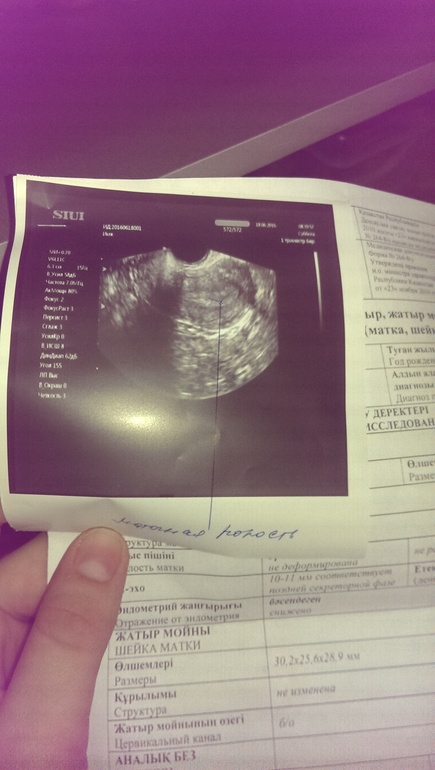

Узи. 12 дз+ би тест.

желтого тела нет,плодного яйца нет. В трубах внематочной нет. Сказал что возможно поздняя овуляция и ребенок не дошел до матки. Жутко боюсь. Девочки,у кого так было и все закончилось хорошо???